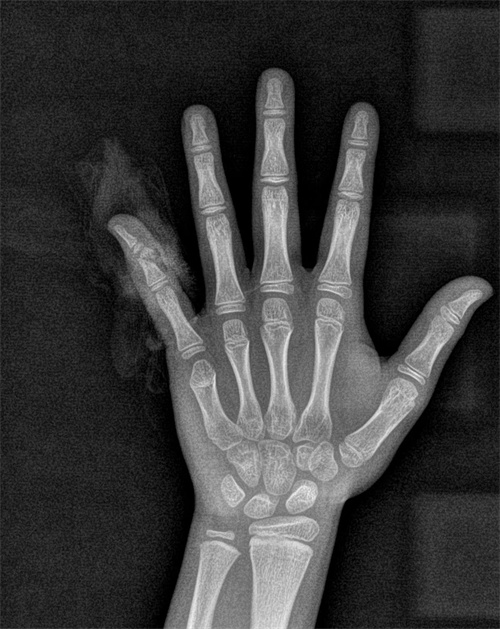

佳佳手术前x线检查结果

8岁的佳佳是个活动好动的小男孩,这个暑假在自家楼下玩滑板车时,因速度未控制好而失去平衡摔倒,左手小指流血不止,被送到捷克论坛 骨科六病区(手足显微外科)就诊,经过仔细检查,发现孩子的小指已经差不多完全断离,经过急诊手术接受了断指再植,将离断的血管和神经接上,才没有影响手指的功能。